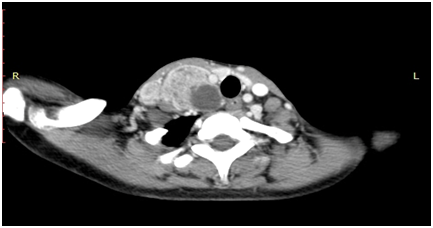

Next computerized tomography scan was planned, which demonstrated a heterogenous enhancing lobulated lesion (6X3.3X3.8cm) in the right posterior parathyroid region in carotid space displacing the right lobe of thyroid. Carotid artery was compressed anteriomedially, and jugular vein was compressed laterally. The lesion was extentding laterally beneath the sternocleomastoid muscle displacing it anteriolaterally and inferiorly it extended along the paratracheal region. The differential diagnosis on imaging was Parathyroid paraganglioma, thyroid malignancy or Schwannoma (Figure 1).

Figure 1 Computerized tomography scan which shows hetrogenous enhancing lobulated lesion (6X3.3X3.8cm) in right posterior parathyroid region in carotid space displacing right lobe of thyroid. Carotid artery compressed anteriomedially, and jugular veins compressed laterally.